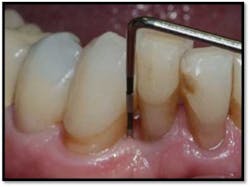

LL Quadrant#27M, now 2mm reduced from 6mm, tissue tight and firm

#26 DF, now 2mm from 8mm

#26 F now 2mm. All tissue is light pink, tight and firm.

Bone fill #26 and 27,no mobility

#18 buccal reflected in a mirror. Now probes 2mm reduced from 9mm